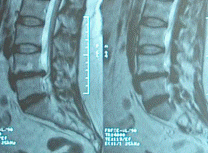

Preoperative extrusion of L4-5, causing drop left foot. Notice the hight of the disc space before the first operation!

2 months after the operation, showing the recurrence. Notice the decrease in the hight of the disc space!